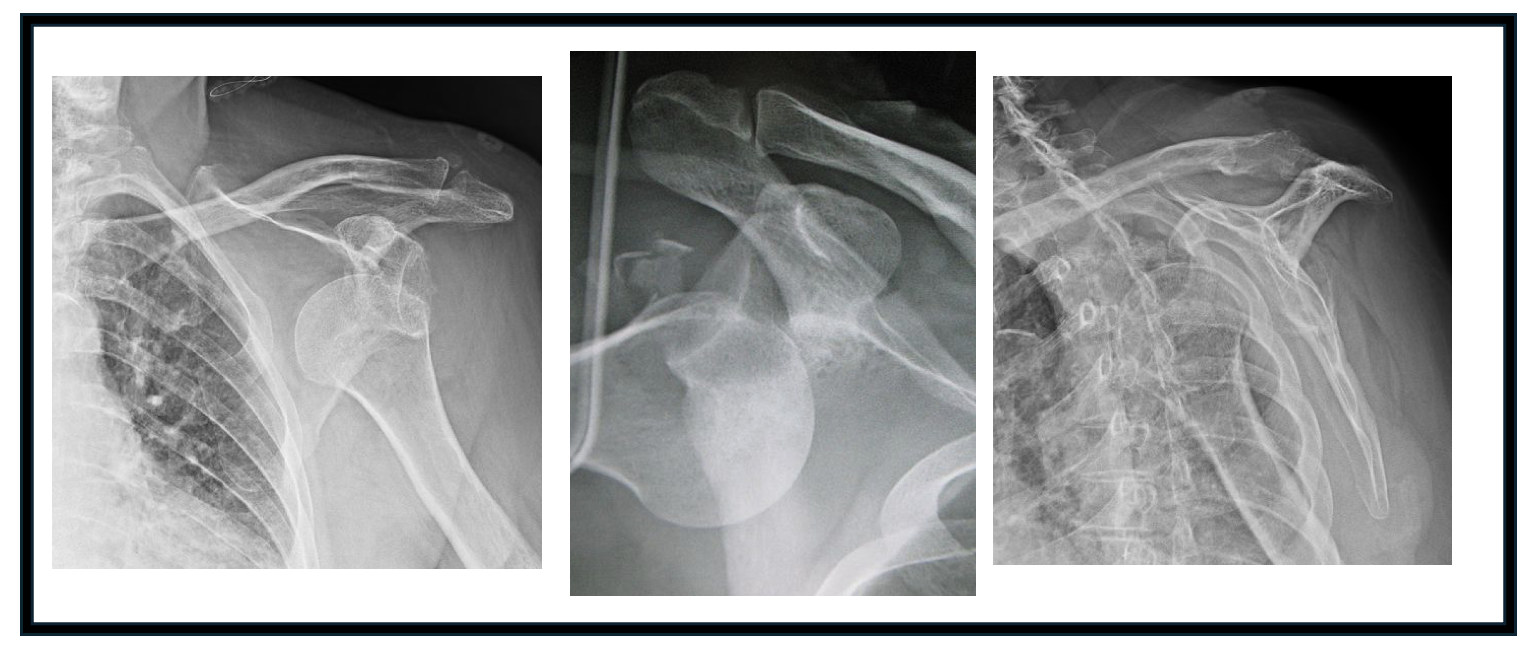

1) X-ray imaging

Plain radiograph imaging is the most common imaging modality used for evaluation of the dislocated shoulder. While there may be clinical signs of dislocation, radiographic imaging is pertinent to obtain at the time of injury and following reduction to ensure appropriate alignment and to evaluate for any fractures. The standard radiographic views should include AP, lateral, axillary and occasionally scapular-Y views. The axillary x-ray is performed with the patient’s arm abducted to about 90 degrees and the x-ray beam is directed into the patient’s axilla. A Velpeau view can be performed if the patient cannot tolerate position arm in space for the axillary view. The obtained image should show the relationship between the glenoid and the humeral head, which can help in the reduction maneuvers. A scapular-Y view is a lateral scapula view with the acromion, coracoid and scapula body forming a “Y” shape. The humeral head (in the non-dislocated setting) should be in the center of the “Y” but may be anterior or posterior to the “Y” when the glenohumeral joint is dislocated. While this view is particularly helpful in differentiating between anterior and posterior shoulder dislocations, it can be difficult to obtain especially when patients are in pain (1-3,25).